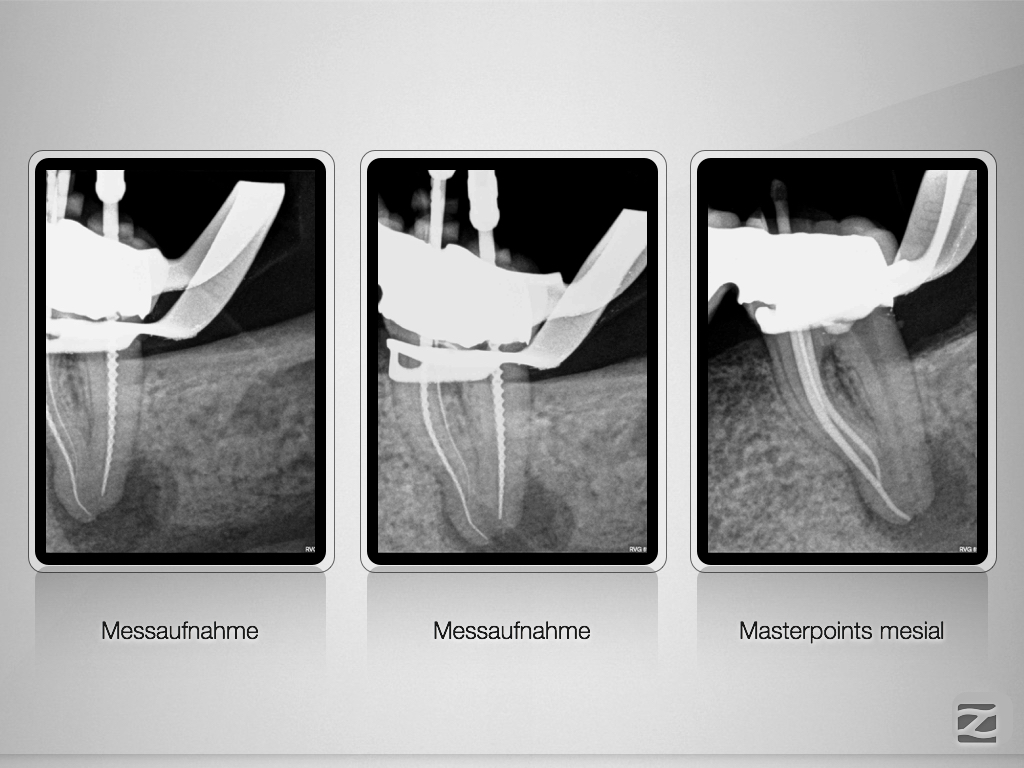

Recall einer ausgedehnten apikalen Lyse